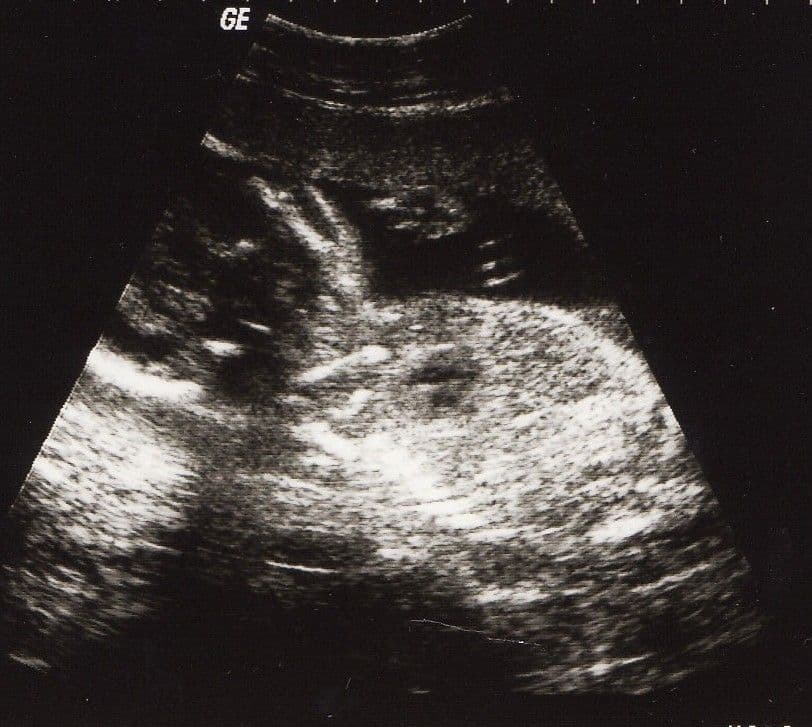

#babavárás#beágyazódás#étkezés#fogamzásA fejlődési rendellenességek@colostok•2011. szept. 13.•1 perc olvasás